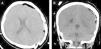

A 19-year-old female with sickle cell anemia (SCD) was referred to our hospital after two days of hospitalization at another hospital for a headache crisis. This headache crisis was due to a raised intracranial pressure; these symptoms were noted and included in her comprehensive list of symptoms. There was an acute drop in the hemoglobin and hematocrit levels. The cranial CT scan demonstrated a left fronto-parietal acute epidural hematoma (AEH) and a calvarial bone expansion, which was suggestive of medullary hematopoiesis. The patient underwent emergent craniotomy and evacuation of the hematoma. There were no abnormal findings intra-operatively apart from the AEH, except skull thickening and active petechial bleeding from the dural arteries. Repeated CT scan showed a complete evacuation of the hematoma. The possible underlying pathophysiological mechanisms were discussed. In addition to the factors mentioned in the relevant literature, any active petechial bleeding from the dural arteries on the separated surface of the dura from the skull could have contributed to the expanding of the AEH in our patient. Neurosurgeons and other health care providers should be aware of spontaneous AEH in patients with SCD.